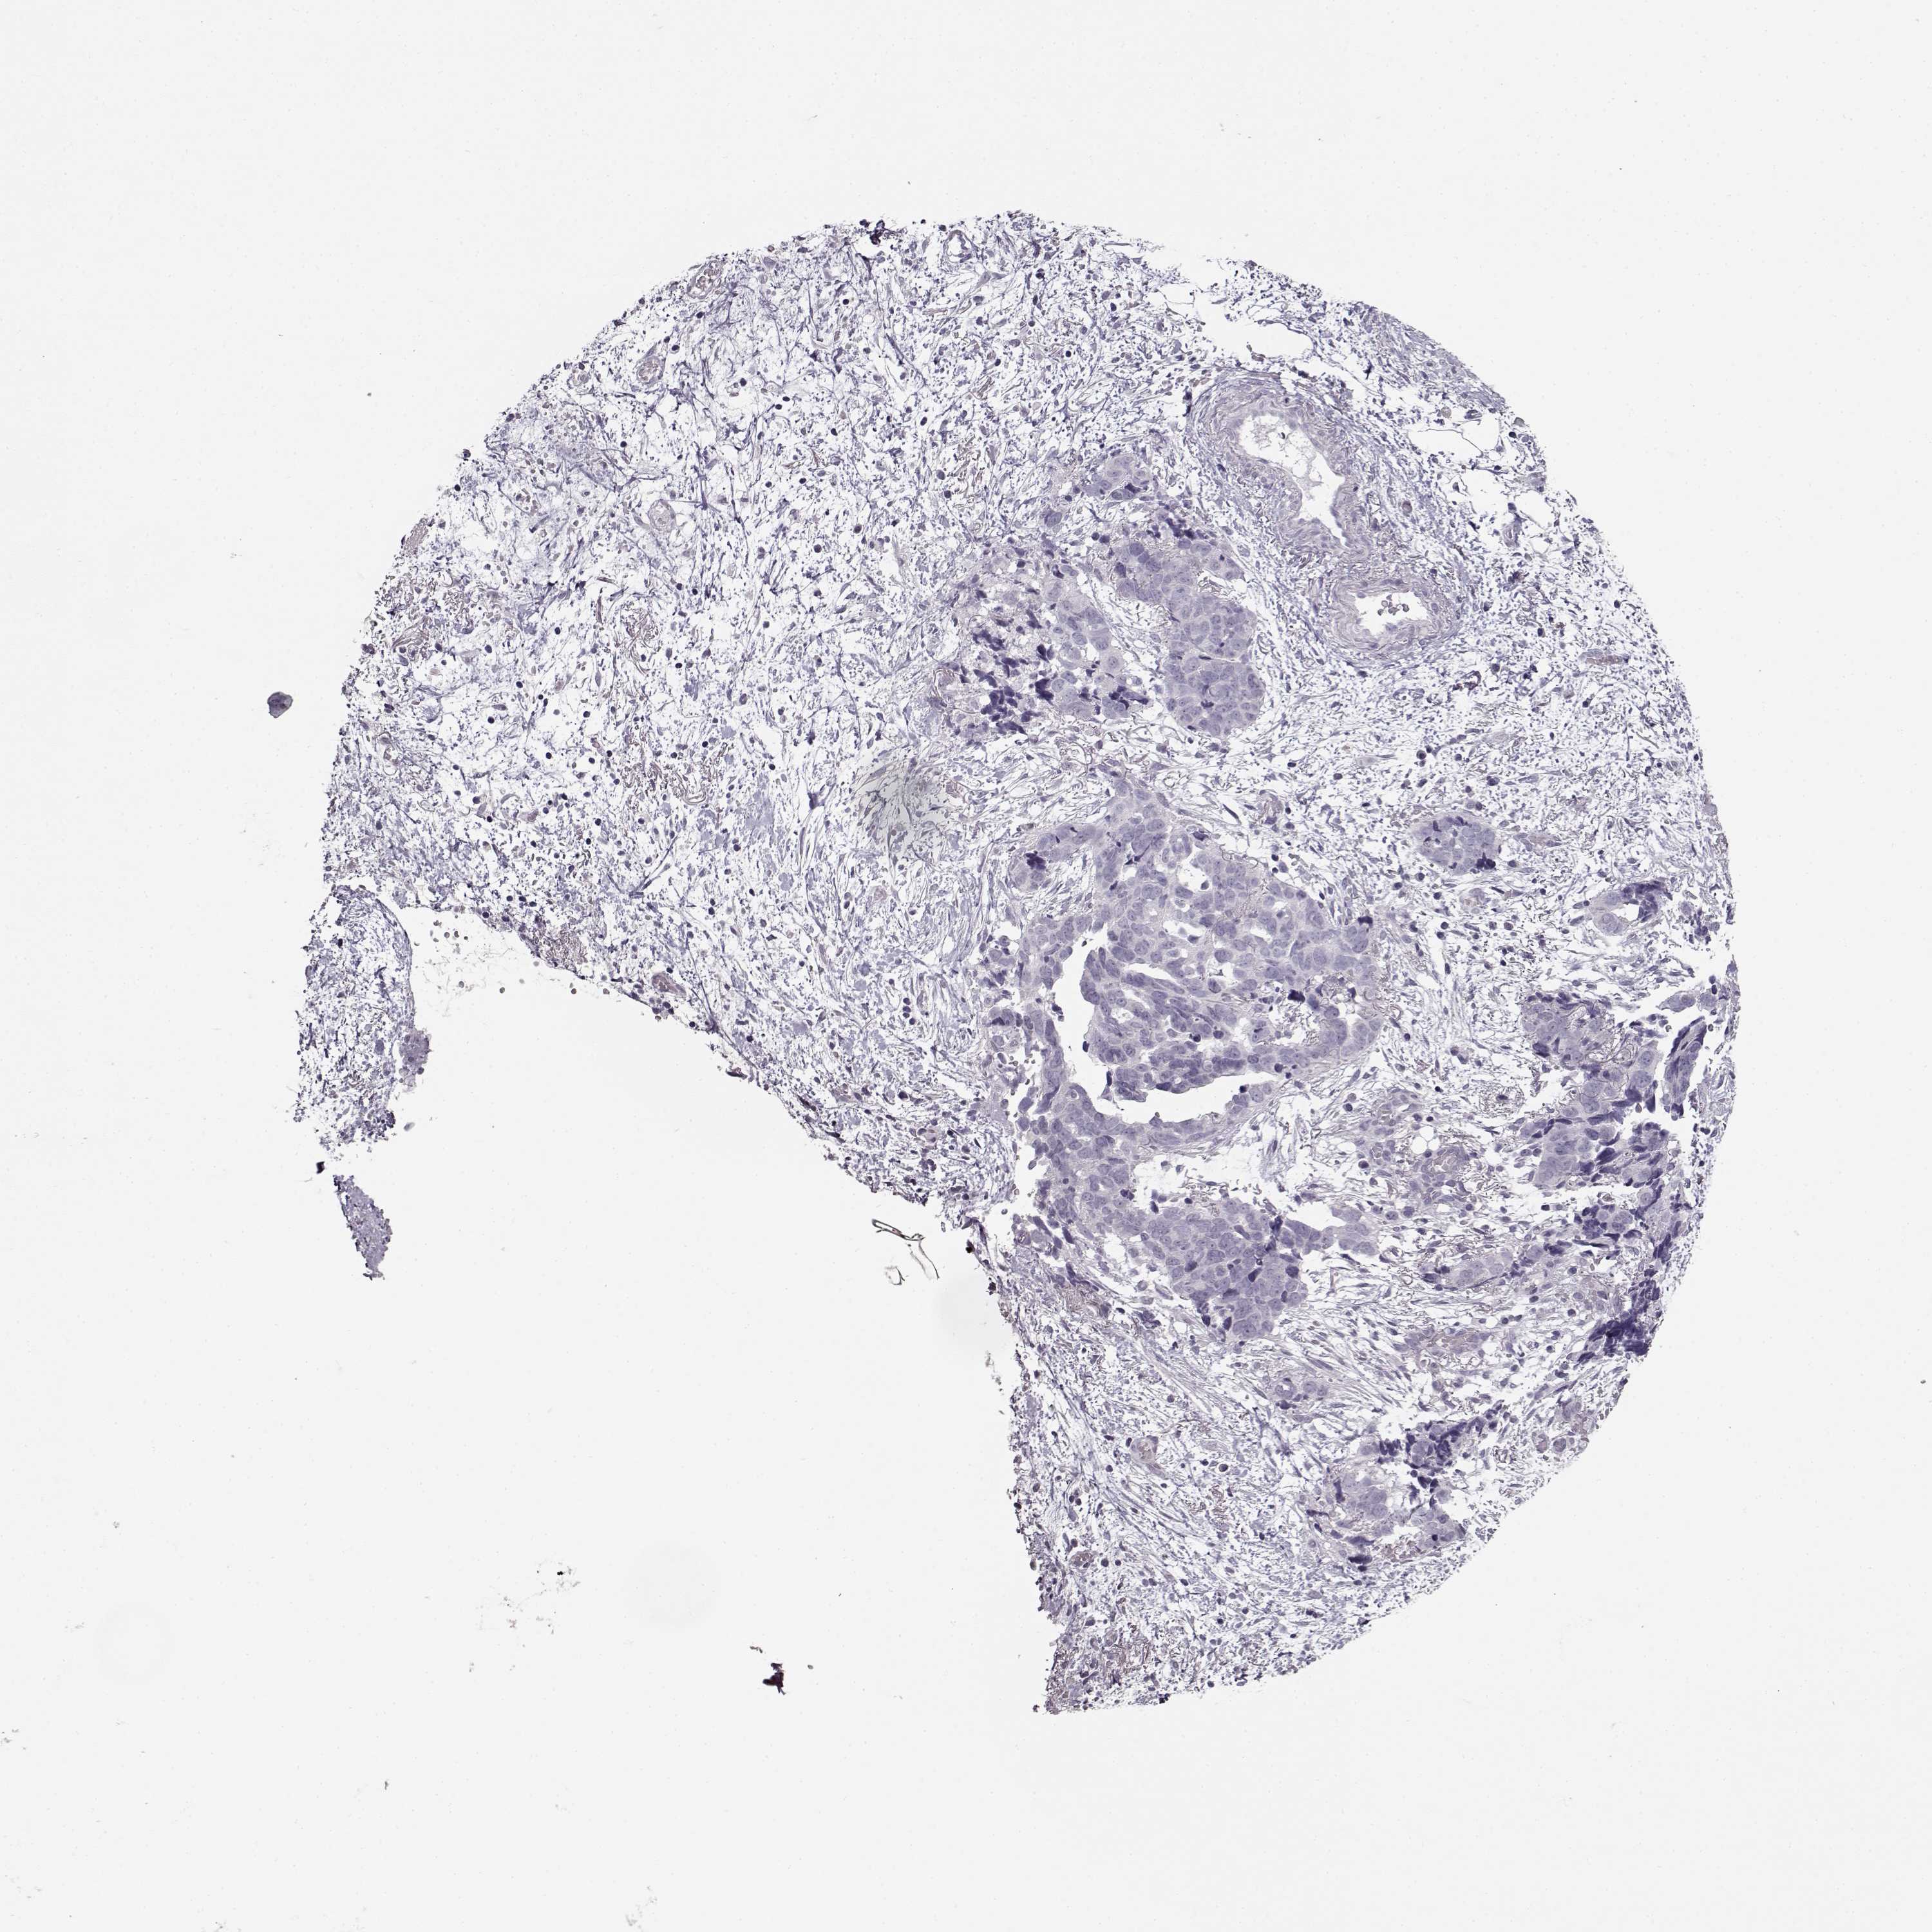

OVARIAN CANCER - Protein expressioni

A mouse-over function shows sample information and annotation data. Click on an image to view it in a full screen mode. Samples can be filtered based on level of antibody staining by selecting one or several of the following categories: high, medium, low and not detected. The assay and annotation is described here.

Note that samples used for immunohistochemistry by the Human Protein Atlas do not correspond to samples in the TCGA dataset.

Antibody stainingi

Antibody staining in the annotated cell types in the current human tissue is reported as not detected, low, medium, or high, based on conventional immunohistochemistry profiling in selected tissues. This score is based on the combination of the staining intensity and fraction of stained cells.

Each image is clickable and will lead to virtual microscopy that enables deeper exploration of all samples and also displays staining intensity scores, fraction scores and subcellular localization as well as patient and tissue information for each sample.

Antibody HPA069703

Antibody CAB023410

Staining

High

Medium

Low

Not detected

Intensity

Strong

Moderate

Weak

Negative

Quantity

>75%

75%-25%

<25%

None

Location

Nuclear

Cytoplasmic/membranous

Cytoplasmic/membranous,nuclear

Cystadenocarcinoma, serous, NOS

Cystadenocarcinoma, mucinous, NOS

Carcinoma, endometroid